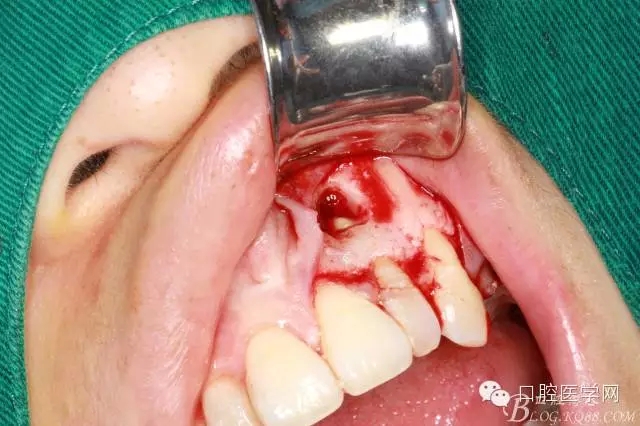

可見囊腫

刮凈囊腫

繼續(xù)去骨暴露牙根

牙根露出3mm左右因為根切長度

沖洗干凈開窗處